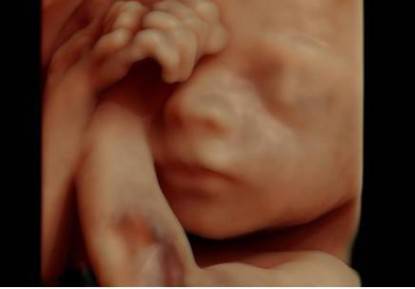

Fino a questo momento la scansione in 3D ci offriva un fermo immagine del feto in 3 dimensioni, ora con l’ecografia in 4D si potrà osservare il piccolo muoversi in tempo reale.

L’immagine diventerà poi più nitida e completa con l’aggiunta di una luce virtuale all’immagine grazie a un software HDLive che calcola la posizione delle ombre e la traslucenza della pelle del bambino.

Il nuovo software così consentirà non solo di osservare l’aspetto tridimensionale del piccolo ma di poter anche ottenere, in pochi secondi, immagini dei vasi sanguigni, degli organi e del cuore.